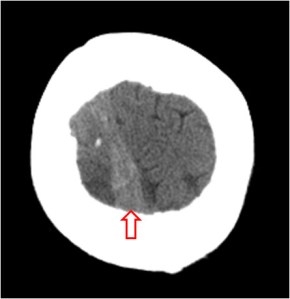

SIGNO DE LA CUERDA

Es un signo visible en la TC craneal sin contraste y que corresponde a pequeñas venas corticales trombosadas. Es un hallazgo poco frecuente consistente en una imagen lineal densa sinuosa que ocupa un surco de la convexidad (flecha), que puede confundirse con hemorragia subaracnoidea. Se observa además una pequeña zona hiperdensa en el lóbulo parietal derecho correspondiente a un infarto venoso hemorrágico.